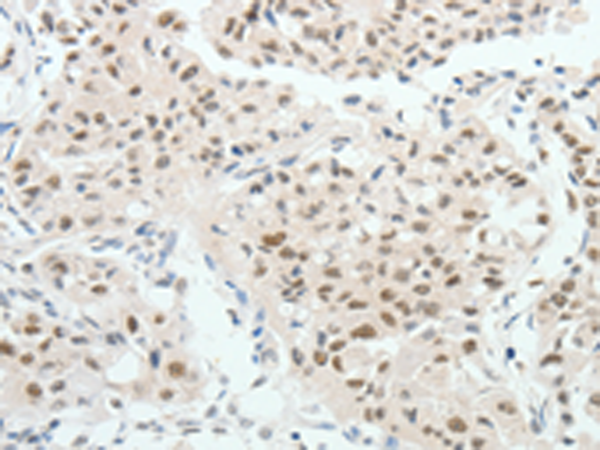

分类: 科研抗体货号: P04219别名: FJHN; HNF2; LFB3; TCF2; HPC11; LF-B3; MODY5; TCF-2; VHNF1; HNF-1B; HNF1beta应用: IHC反应种属: Human, Mouse, Rat